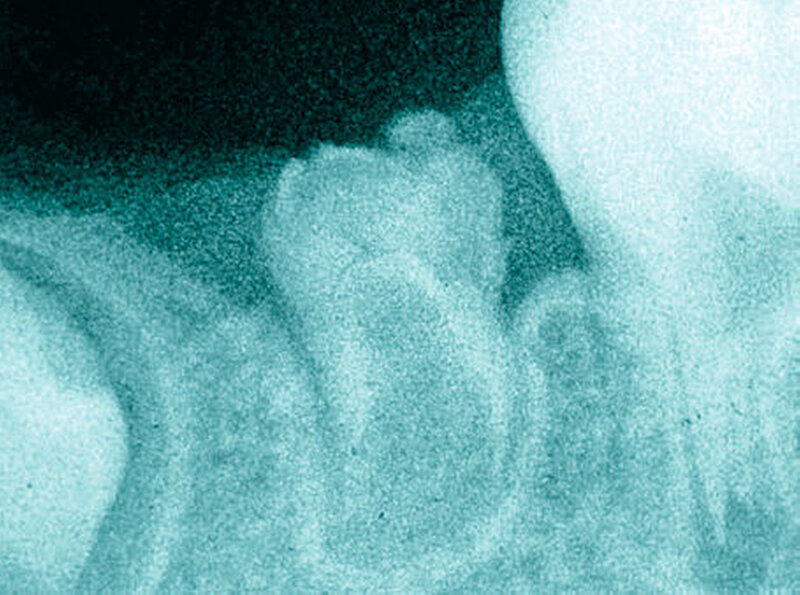

Im Röntgenbild kann der Schmelz kaum vom Dentin unterschieden werden. Die Zähne erscheinen verschwommen und fleckig. Dies führt zu einem geisterhaften Erscheinungsbild, weshalb solche Zähne auch „ghost teeth“ genannt werden (Abbildung 13). In der Pulpa findet man häufig Dentikel (Abbildung 15). Die stark verkürzten Wurzeln haben ein weit offenes Foramen apicale (Abbildung 15).